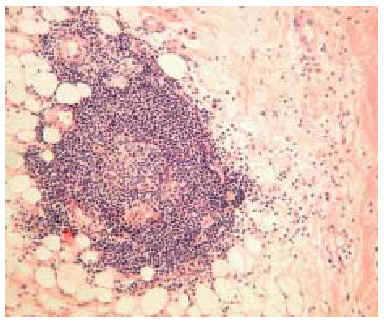

En septiembre de 1999 presentó un nuevo brote de lesiones cutáneas clásicas de dermatomiositis, así como 5 lesiones nodulares en ambos miembros superiores, de unos 3 cm de diámetro, dolorosas, induradas, de superficie poiquilodérmica, sin sintomatología muscular ni elevación de las enzimas musculares. Se realizó una biopsia cutánea de un nódulo del brazo que puso de manifiesto una degeneración vacuolar focal de la capa basal epidérmica y un leve infiltrado inflamatorio linfohistiocitario perivascular en la dermis. Lo más llamativo fue la presencia de una paniculitis de predominio lobulillar con linfocitos, histiocitos y células plasmáticas (fig. 2). En algunas zonas los linfocitos formaban acumulaciones donde se insinuaba un centro germinal (fig. 3) y en otras infiltraban la pared de los vasos (fig. 4).

Fig. 2.--Paniculitis lobulillar con linfocitos y células plasmáticas. (Hematoxilina-eosina, x40.)